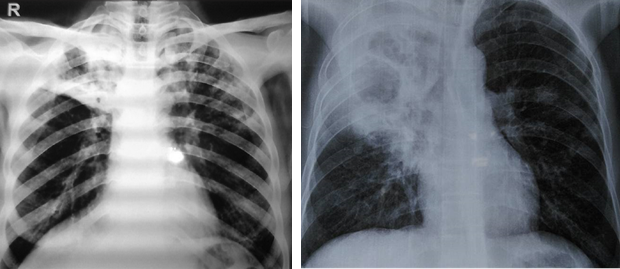

Viêm phổi: thường gặp nhất (50%)

+ khởi phát là tình trạng ho khan hoặc kèm máu, sốt, khó thở, đau ngực kiểu màng phổi, có thể kèm các biểu hiện của tình trạng nhiễm khuẩn mạn tính như sụt cân, ra mồ hôi trộm.

+ viêm phổi thường không điển hình, ít khi có đau ngực hay có HC đông đặc như viêm phổi thuỳ

+ Xquang: thâm nhiễm lan toả hoặc tổn thương đông đặc rải rác 1 hay vài thuỳ phổi, thường gặp ở thuỳ trên, có thể kèm tràn dịch, tràn mủ màng phổi; hoặc tổn thương dạng hang áp xe